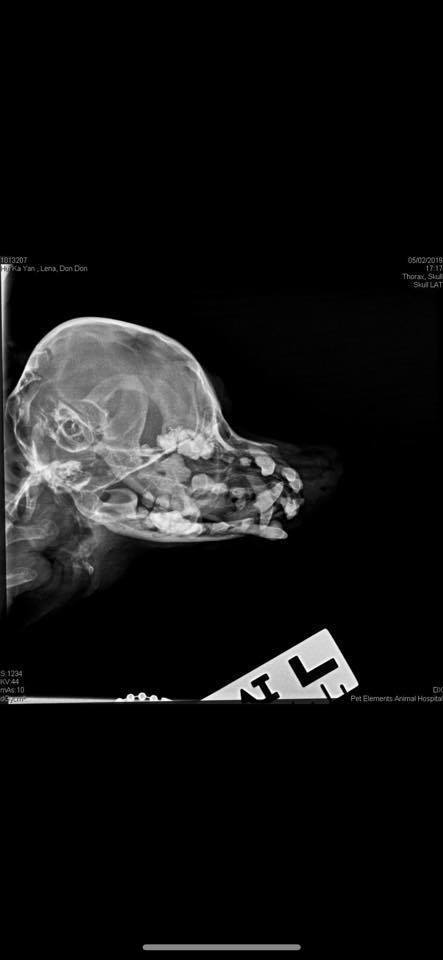

根據網友許小姐在帖文中形容,兩隻狗狗當時身體虛弱之餘,身型亦偏向瘦削,其中一隻狗狗Dong Dong精神不太好,只見牠常縮在一角睡覺,更發現在牠睡覺的地方沾上一些從狗狗的口腔內流出來的白色膿液。原來狗狗口腔內全是爛牙,不斷有膿和血水滲出,Dong Dong亦因口腔潰爛導致食慾不振。許小姐試圖強行把藥和食物餵到牠的喉嚨,但一邊餵,口腔不斷有血水滲出,而且狗狗亦痛到不能把口合起來,情況叫人慘不忍睹。

至於King King ,牠的情況就較為好一些,雖然同樣口內有血水,全都是爛牙,但至少牠精神狀態較好,而且亦有食慾,但不幸的是,經檢查後發現King King有輕微腎石的問題。

另外,Dong Dong、King King兩犬都有隱睪症問題,如果任由問題不處理的話,在製作精子時會容易引致基因出錯,長遠而言會促使形成腫瘤和增加患癌的機會。

兩隻狗狗情況並不樂觀,然而始終許小姐不是原狗主,要為狗狗做麻醉手術之前,必須先得到狗主同意。根據帖文指出,獸醫診所其後透過狗狗身上的晶片找到登記主人,登記主人是一位中學生,兩隻狗狗是由登記主人的媽媽所養,由於要搬公屋所以不能再養牠們,而狗狗就被丟棄在一間空屋內兩個月,只靠朋友上來提供糧食和食水。網友許小姐在帖文中表示,雖然晶片資料顯示狗狗只得5-6歲,但牠們的健康情況就似十幾歲般,對於狗狗的遭遇感到十分心痛。